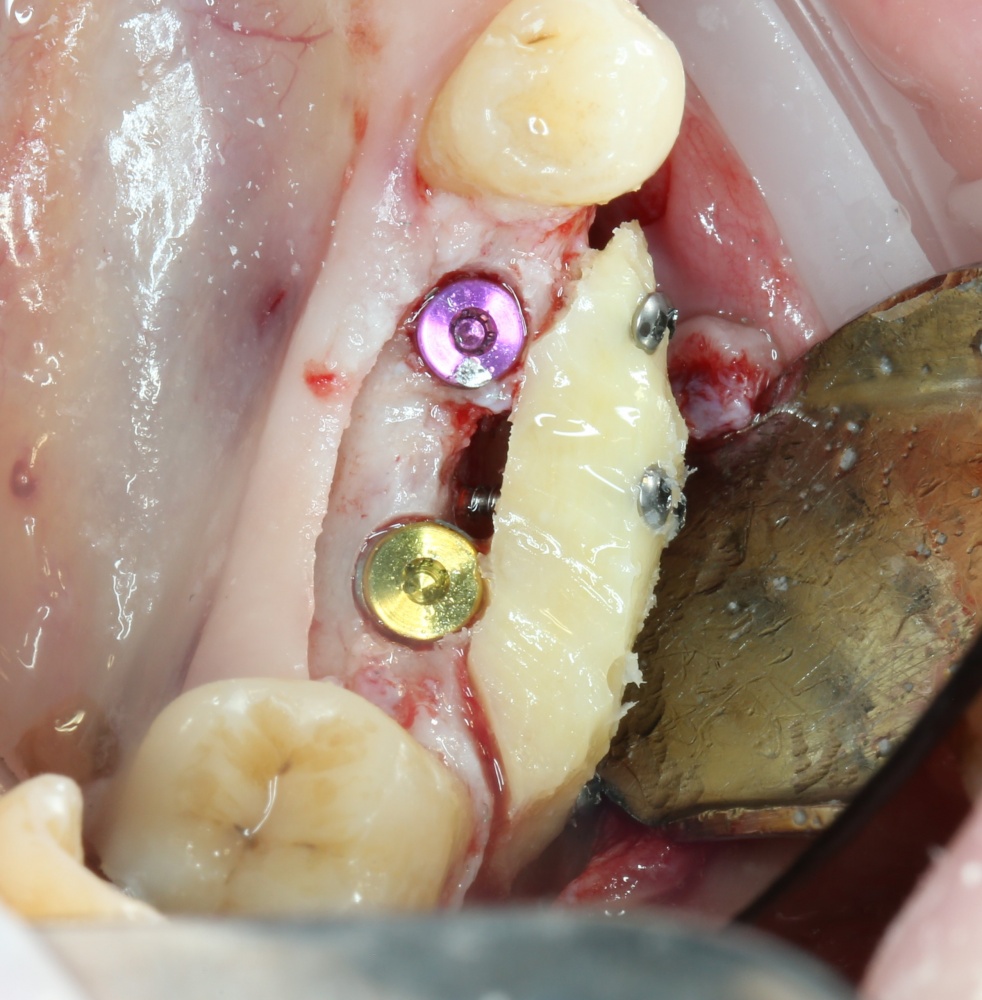

Следующим этапом происходит формирование и забор аутокостного фрагмента для пересадки:

A09A5447 (2) A09A5448 (2)

Далее, примеряем и адаптируем костный блок:

A09A5449 (2) A09A5450 (2)

Готовим его к фиксации:

A09A5451 (2)

Многие ошибочно предполагают, что большое количество дырок в блоке нужно для того, чтобы «всё лучше срослось». На деле, большое количество отверстий в аутокостном фрагменте даст нам возможность переставлять вины и адаптировать его «на месте». А это особенно важно для одномоментной установки имплантов, потому что винты не должны попасть в проекцию будущей лунки.

Фиксация костного блока:

A09A5452 (2) A09A5453 (2)

Для этого стоит использовать длинные винты. В противном случае, при подготовке лунки под имплантат костный блок может отлететь.